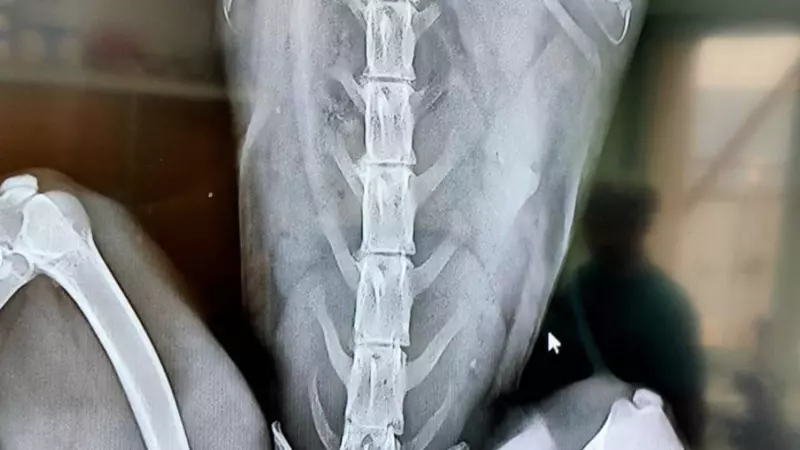

«Лисица, молодая самка. Перелом шейного позвонка, в области спинных позвонков видна пуля (дробь). Мы не знаем, в какой последовательности она получила эти повреждения, но точно знаем, что её щенки обречены - лиса оказалась кормящая», – констатировали специалисты в Instagram-аккаунте fond_greensakhalin.

Они добавляют, что сейчас за состоянием лисицы необходимо наблюдать в динамике. Ей сделана фиксация позвоночника, лечение рыжая получает в полном объеме.